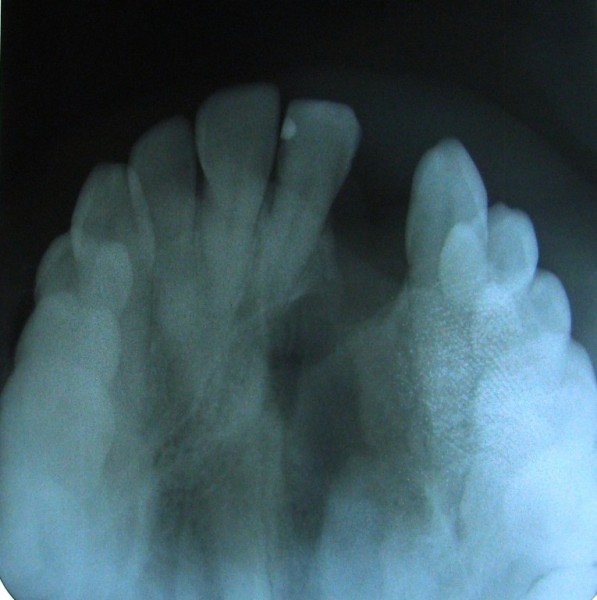

Alveolar Cleft (Defect in the Upper Jaw) Repaired with a Hip Bone Graft

Before